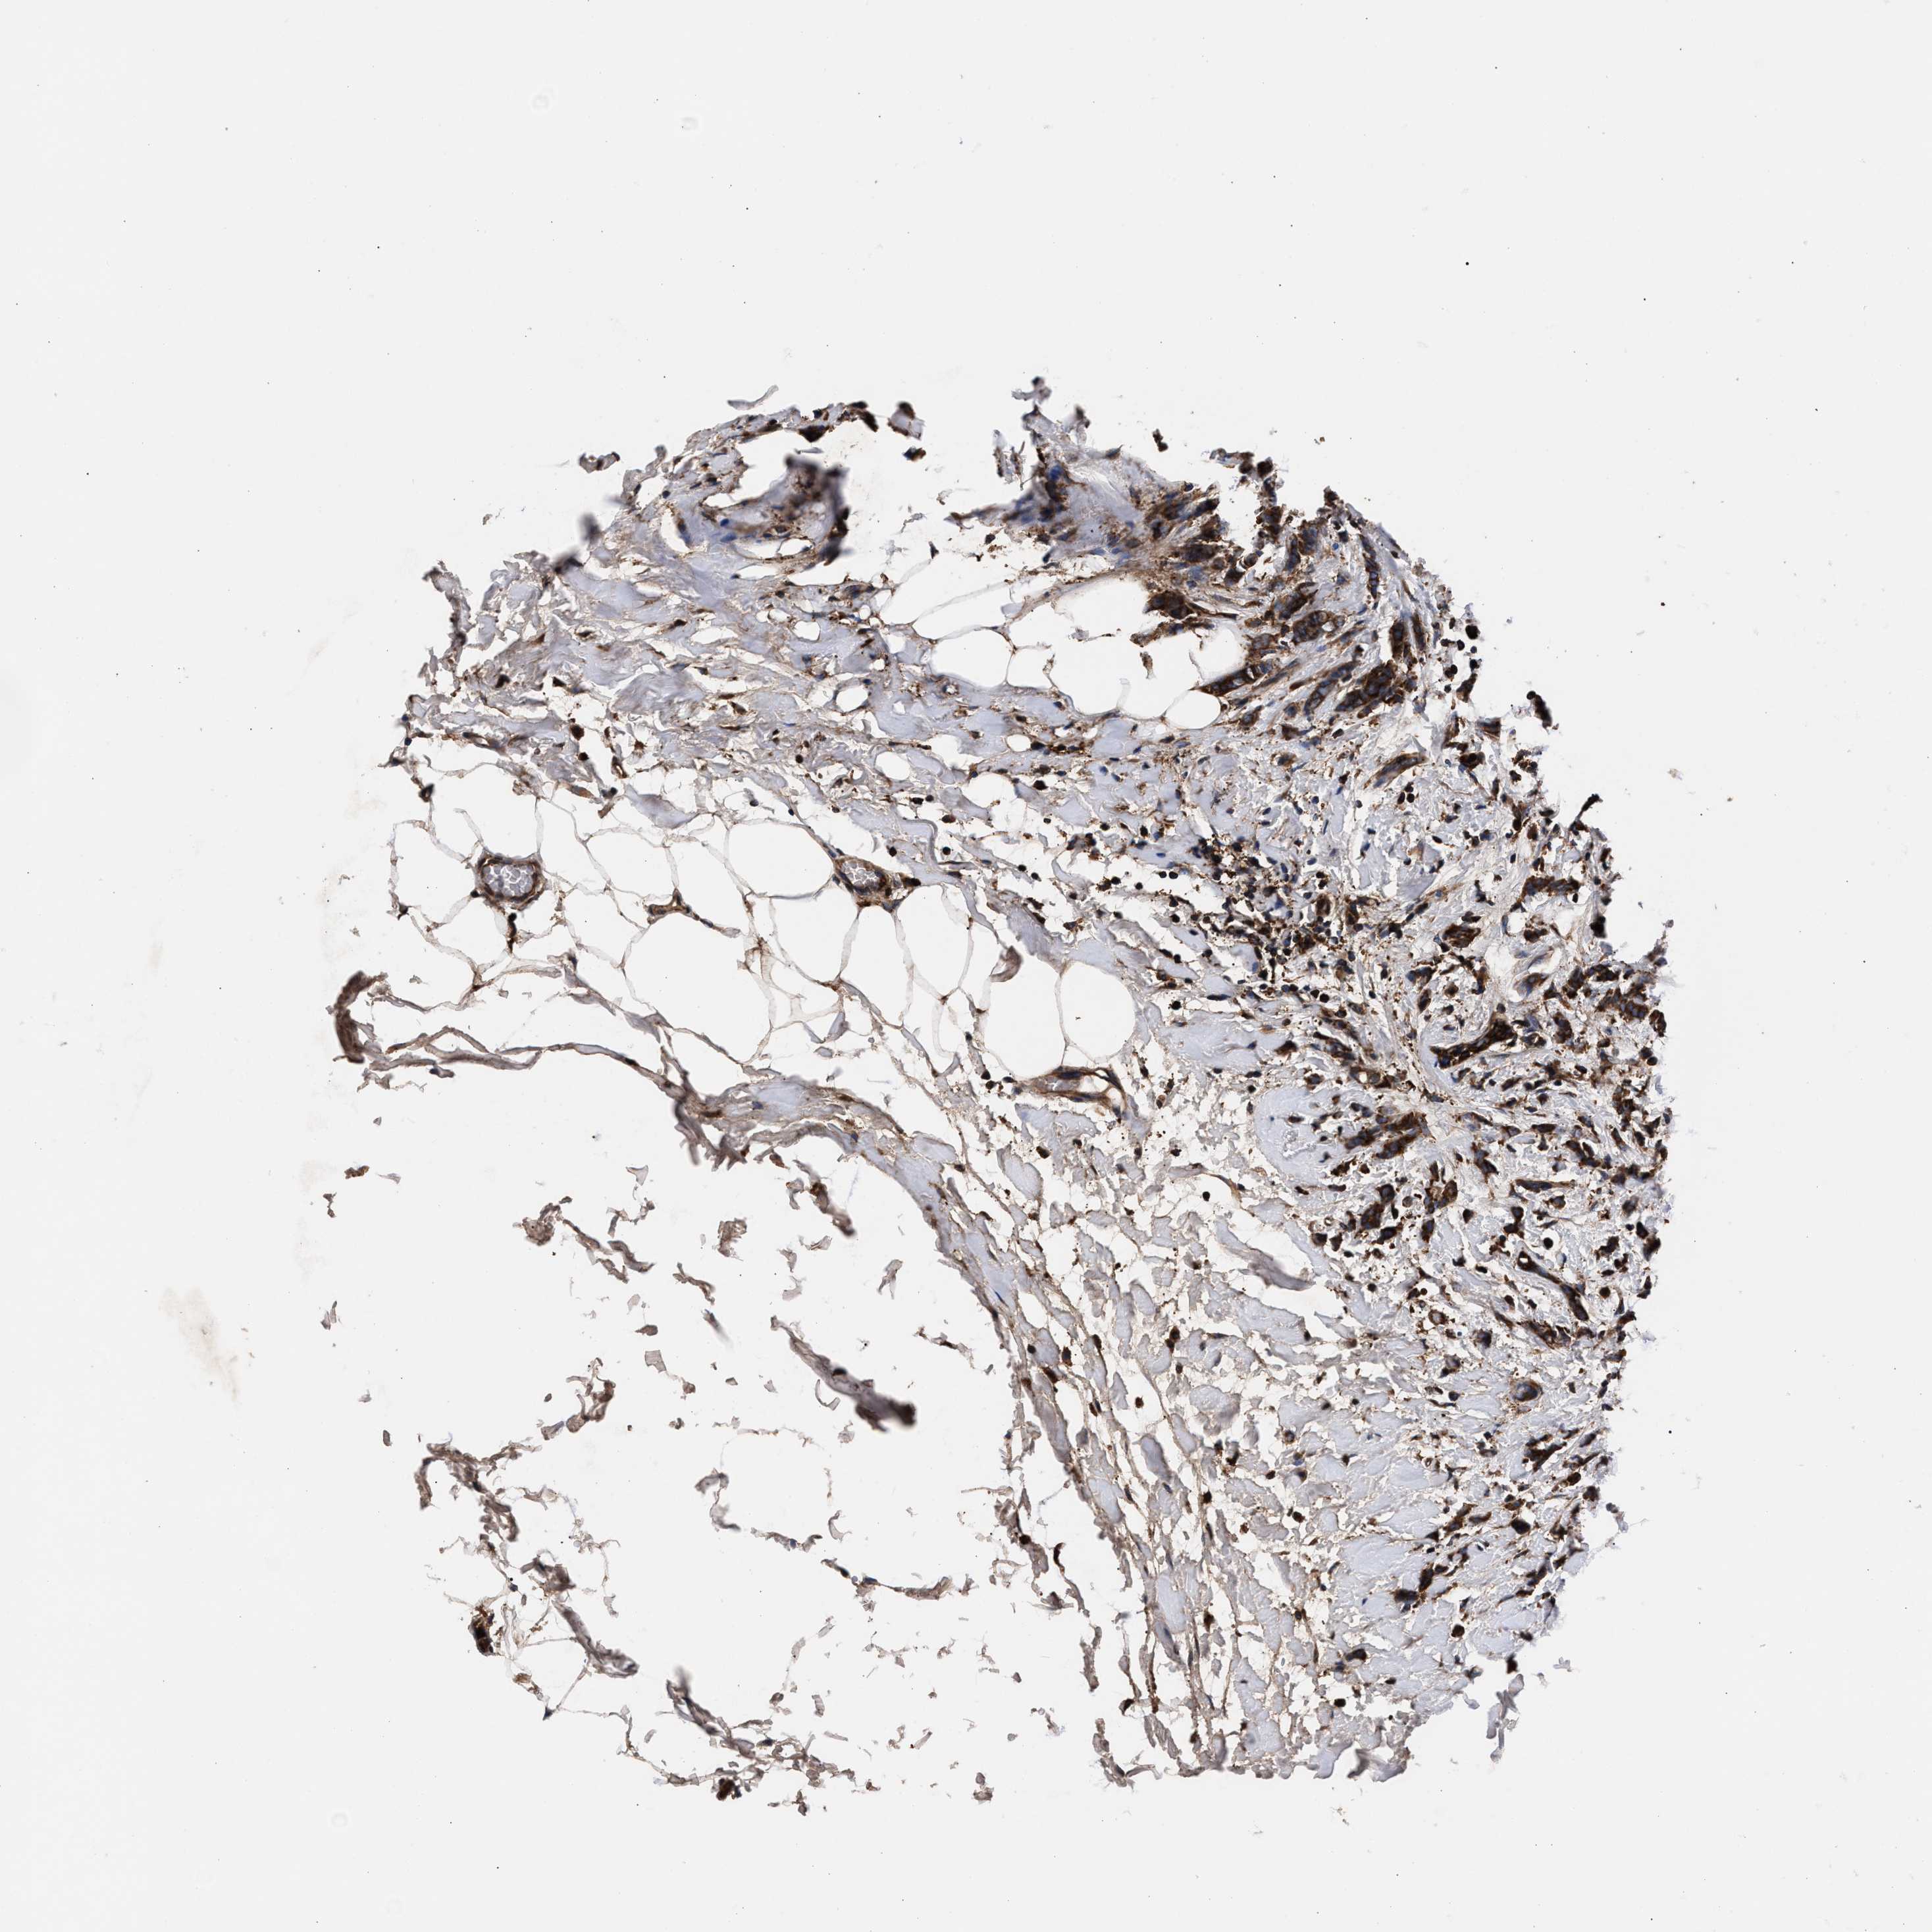

BRCA TCGA BRCA VALIDATION PROTEIN EXPRESSION

ANTIBODIES

AND

VALIDATION